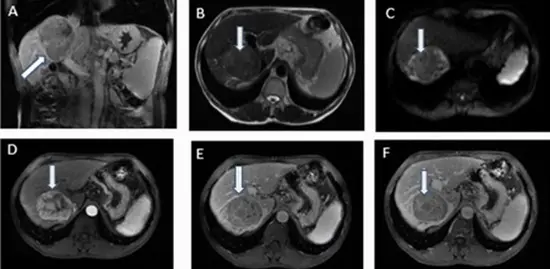

Comparing Texture Analysis of Apparent Diffusion Coefficient MRI in Hepatocellular Adenoma and Hepatocellular Carcinoma

Aim: This study aimed to assess the effectiveness of using MRI-apparent diffusion coefficient (ADC) map-driven radiomics to differentiate between hepatocellular adenoma (HCA) and hepatocellular carcinoma (HCC) features.

Materials and methods: The study involved 55 patients with liver tumors (20 with HCA and 35 with HCC), featuring 106 lesions equally distributed between hepatic carcinoma and hepatic adenoma who underwent texture analysis on ADC map MR images. The analysis identified several imaging features that significantly differed between the HCA and HCC groups. Four classification models were compared for distinguishing HCA from HCC including linear support vector machine (linear-SVM), radial basis function SVM (RBF-SVM), random forest (RF), and k-nearest neighbor (KNN).

Conclusion: The study found that utilizing ADC maps for texture analysis in MR images is a viable method to differentiate HCA from HCC, yielding promising results in identified texture features.